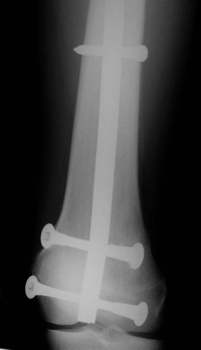

Acht Monate nach der Operation wurde das Metall entfernt.

Die Entfernung durch das Knie hindurch machte keine Probleme. Der

Patient konnte nach 8 Tagen das Knie wieder frei bewegen. Da das Wachstum

weitgehend abgeschlossen war, gab es keine Beinlängendifferenz.